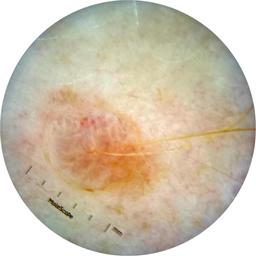

ISIC_7193897

1979 x 1979

Clinical

Field Value

acquisition_day 251

age_approx 65

anatom_site_1 Lower extremity

anatom_site_general lower extremity

concomitant_biopsy False

diagnosis_1 Benign

diagnosis_confirm_type single image expert consensus

family_hx_mm False

image_manipulation instrument only

image_type dermoscopic

lesion_id IL_3780211

patient_id IP_3751325

personal_hx_mm True

sex female